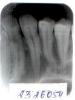

DieHard Опубликовано 29 мая, 2011 Автор Поделиться Опубликовано 29 мая, 2011 Данные куда более чем объективные. До мелочей.Что касается анамнеза.. в целом по зубам есть такая таблица (в приложении)По зубу - в тексте все подробности, что я слышал от врача и что врач говорил мне. Помогите, помру) Ссылка на комментарий

DieHard Опубликовано 30 мая, 2011 Автор Поделиться Опубликовано 30 мая, 2011 Новости с фронта.В главной клинике врач тоже сказала, что зуб открытым на такой срок большой оставлять нельзя как мне сделали.Посмотрела снимок и увидела, что очаг всё таки большей частью был не у клыка, а у зуба рядом. Не знаю какой цифрой он называется... фигурировали "в деле" 22 и 23.Говорит: "Жалко же его вскрывать...". Потом пошатала его и говорит, мол, нет, надо вскрывать, зуб шатается. Ну и вскрыла... а там... а там зеленый гной вперемешку с кровью хлынул просто... Ну в общем канал клыка запломбировала "розовой" пломбой.. между собой они его каким-то "матафиксом" называли чтоли... (Ах да.... он плохо был вычищен... не до конца... так что подчищала его) Второй зуб оставила открытым... слишком много гноя... не прекращал идти... сказала, если ставить вр. пломбу, то вдруг воспалиться десна и тогда уже в хирургию вскрывать десну.Зуб полоскать 1,5 дня и к ней на пломбировку второй зуба. А потом... через месяц к ней, ставить постоянные пломбы. А ещё эта умничка мне даже укольчик сделала))) Девочка молодая, понравился я ей наверно))) Ссылка на комментарий